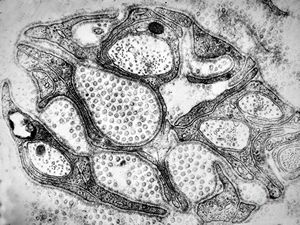

F,49y. | purulent meningitis- meningococcal v.s.